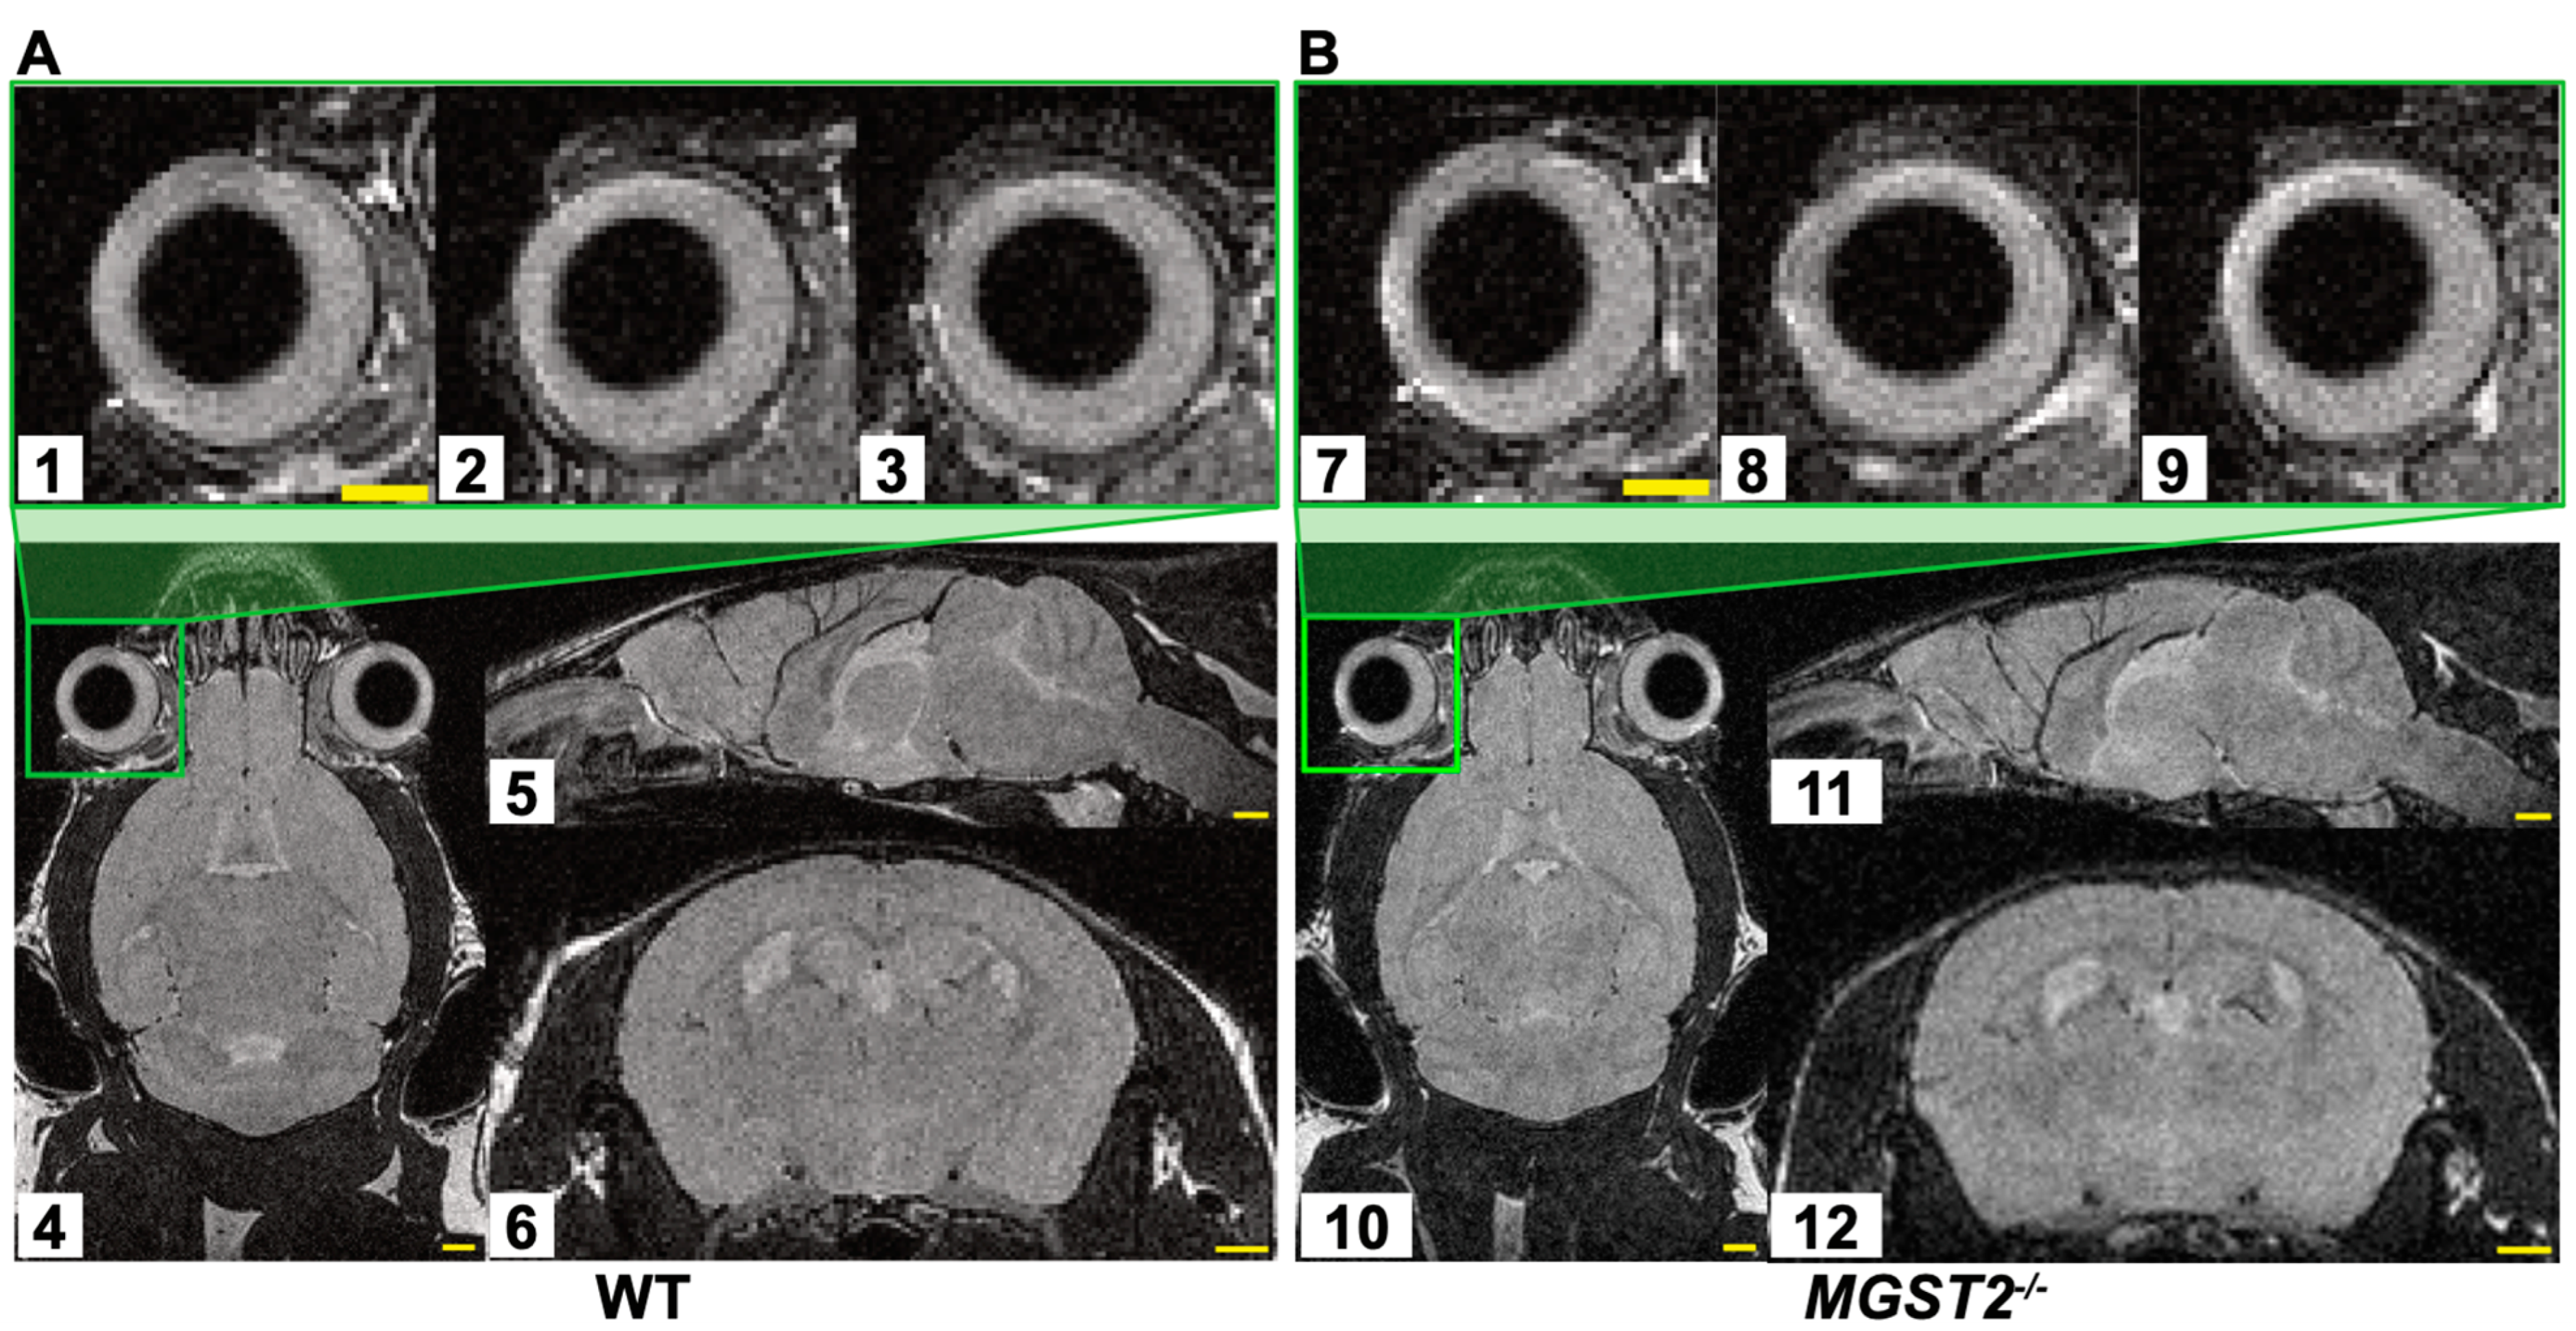

3.2. Magnetic Resonance Imaging of the Mice Eyes